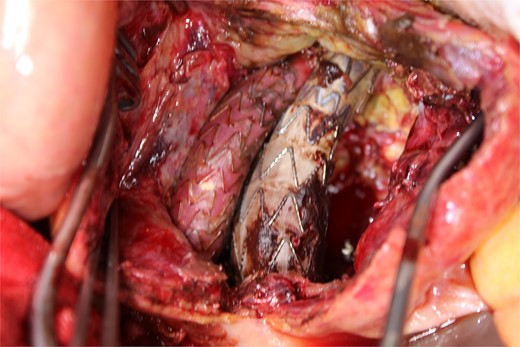

This time, he was brought to the emergency department with a chief complaint of abdominal pain. His medical history includes Stage 4–5 chronic kidney disease (CKD), with an estimated glomerular filtration rate (eGFR) of approximately 15 mL/min/1.73 m2, secondary to nephrosclerosis and diabetic nephropathy, as well as persistent atrial fibrillation, which was treated with warfarin. Upon admission, laboratory results revealed a hemoglobin level of 6.2 g/dl and a prothrombin time—international normalized ratio (PT-INR) of 6.05. Contrast-enhanced CT demonstrated an AAA measuring 118 × 107 mm, enlarged from 98 × 94 mm 2 months prior, and left retroperitoneal hematoma. IMA and one pair of lumbar arteries were enhanced only in the delayed phase, but blood flow into the aneurysm was not clearly observed (Fig. 1). Given that the landing zones and overlaps of the stent grafts were satisfactory (Fig. 2) and that no type I or type III endoleaks were identified, a ruptured AAA due to TIIEL from the lumbar artery or IMA was highly suspected. We administered 3000 IU/kg of lyophilized human prothrombin complex concentrate in response to the significant prolongation of PT-INR and proceeded with open surgery for ligation of the feeding artery and aneurysmorrhaphy. Intraoperatively, no pulsation was found on the aneurysm. Incision of the aneurysm revealed a large amount of thrombus, which was removed, and then pulsatile bleeding was identified from a lumbar artery (Fig. 3), the ostium of which was sutured from within the aneurysm. This was consistent with the left lumbar artery of the pair enhanced on the preoperative CT and was suspected to be responsible for the rupture. Oozing was also noted from several other lumbar arteries, which were similarly sutured closed. No leak was observed from the proximal or distal ends, nor from the junctions of the stent grafts, and no damage to the stent grafts was observed (Fig. 4). Following this, aneurysmorrhaphy was performed, and the abdomen was closed. The postoperative course was uneventful. A plain CT on postoperative day (POD) 14 showed a reduction in the aneurysm size with no apparent leaks (Fig. 5). The patient was discharged home on POD 24. Although the preoperative eGFR was 8.8 ml/min/1.73 m2, no postoperative deterioration was observed. It gradually improved back to baseline, and dialysis was not required during the follow-up period.

A photo taken from the cranial side of the patient. A jet of bleeding was identified from a lumbar artery.